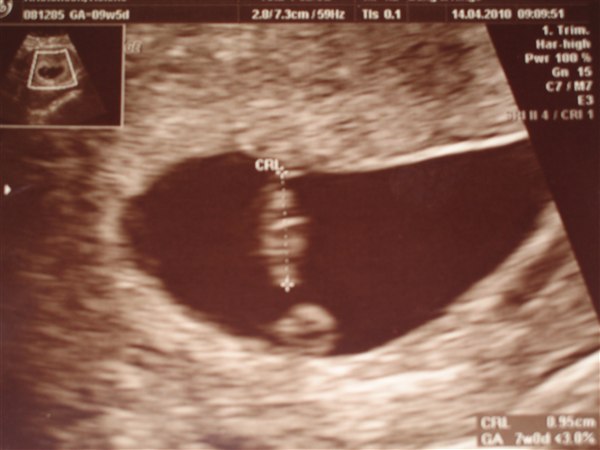

hej som i alle ved så var jeg til scanning idag. det gik rigtigt godt det lille hjerte bankede der ud af også sat hun mig lige 14 dage tilbage næsten 2,5 uge til bage jeg troede at jeg var i uge 9+5 men jeg er kun i 7+1 idag, men alt var godt og der var ingen tegn på at det var uden for livmoren jeg har lige lagt et billede ind på billede er den 1 cm så det er rigtigt dejligt at være opklaret og alt er godt

Vedhæftede fotos (klik for at se i fuld størrelse)